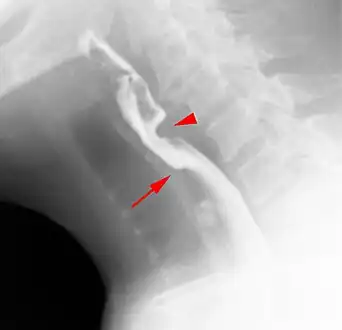

Esophageal web stenosis in barium swallow examination lateral view.

Web with "jet-phenomenon". Arrowhead on incomplete opening of the upper esophageal sphincter.